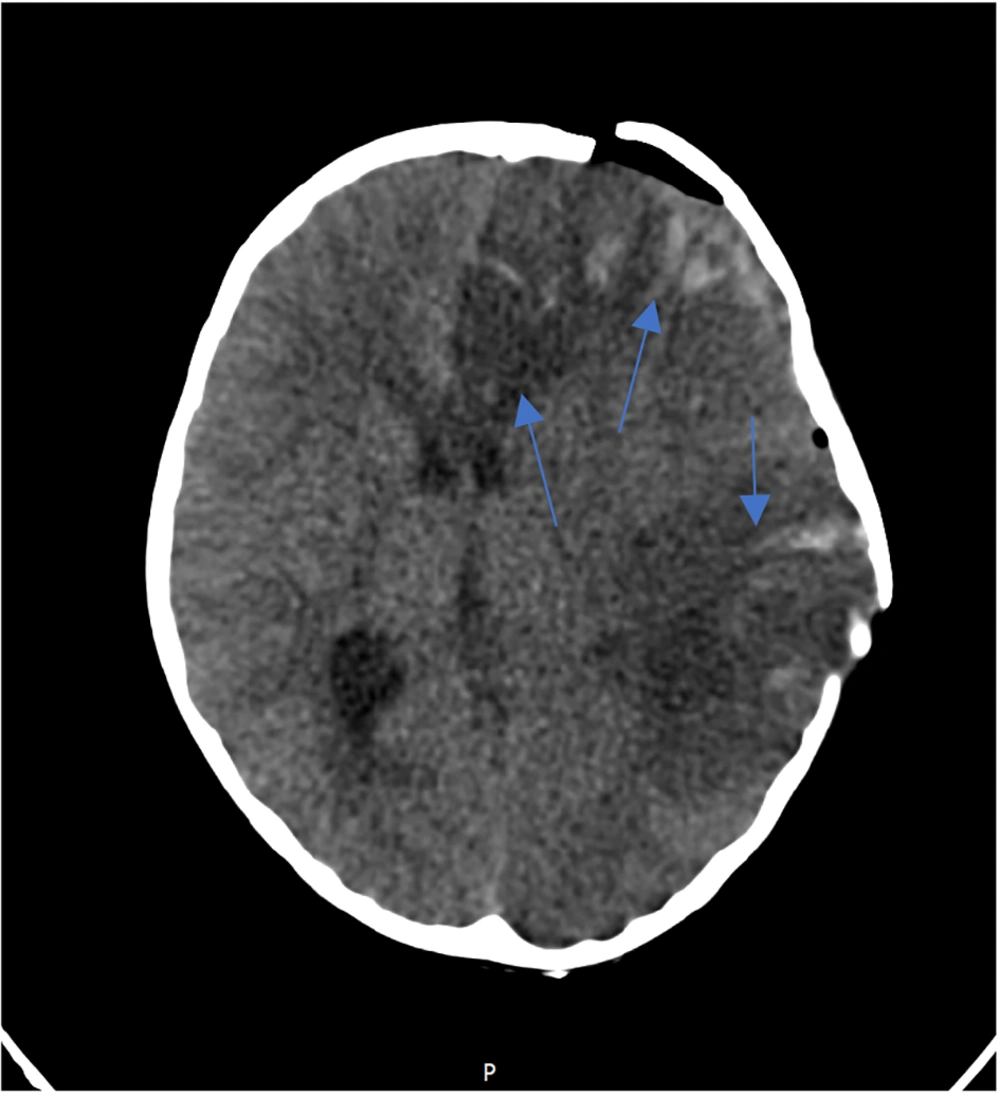

Three days after successful extubation, the patient demonstrated abnormalities in limb tone and force, as well as anisocoria. Brain MRI showed severe generalized edema, ischemia, and herniation (Figure 2). Antiepileptic drugs were started due to brain damage. Following a severe increase in intracerebral pressure, a craniotomy was performed, and supportive treatment continued. A brain biopsy showed inflammation and bleeding. MRA (Magnetic Resonance Angiography) showed a filling defect in the right vertebral artery. Post-craniotomy MRI reported mild herniation through the craniotomy site. An abnormal T2/FLAIR high signal was noted in the left cerebral hemisphere, left basal ganglia, and left thalamus as a sequel of infarction. Hemorrhagic changes in the left frontal lobe were seen, with multiple areas of gyral T1-high signal mostly suggestive of cortical laminar necrosis (Figure 3). There were no changes in favor of HSV in the MRI. Post-craniotomy CT scan showed parenchymal edema and hemorrhagic changes in the left frontal lobe, with abnormal hyper-dense foci noted in the genu and splenium of the corpus callosum and left caudate nucleus (Figure 4). The patient was diagnosed with cerebral stroke. CSF PCR for HSV from the brain biopsy, serum HLA B51, IgA, IgG, IgM, IgE, ANA, lupus anticoagulant, TG, cholesterol, HDL, LDL, pANCA, cANCA, anti-coagulant IgG and IgM, anti-cardiolipin IgG and IgM, protein C, protein S, anti-thrombin 3, F-ANA, anti-B2 glycoprotein, anti-DNase, IL-6, and anti-Smith were performed (Table 1).